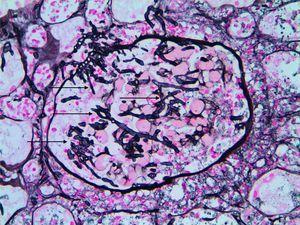

Los resultados de laboratorio mostraron hemoglobina de 88 g/l (8,8 g/dl), plaquetas 45 000 células/μl, leucocitos 7200 células/μl (linfocitos 240 células/μl), proteína C reactiva 254,7 mg/l (25,4 mg/dl) y antigenemia para citomegalovirus positivo. La radiografía de tórax mostró infiltrados pulmonares bilaterales (figura 1). Se inició tratamiento antibiótico de amplio espectro y ganciclovir. Dos días después de su ingreso, la detección del antígeno galactomanano de Aspergillus en suero y el lavado broncoalveolar resultaron positivos y se añadió voriconazol y caspofungina. Sin embargo, el paciente evolucionó rápidamente hacia un shock séptico y murió en cinco días. La necropsia mostró aspergilosis diseminada en los pulmones, los ganglios mediastínicos, la tiroides y en el injerto (figura 2) asociada con infección por citomegalovirus pulmonar y esofágica.

Figura 2. Examen posmuerte del injerto renal que muestra aspergilosis invasiva. Las flechas apuntan a hifas en el glomérulo. Técnica de plata, x400.